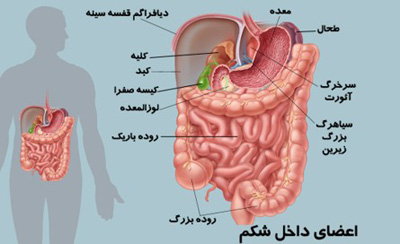

عکس داخل شکم انسان. در این همان طور که مشخص است شکم حالت بیضی شکل پیداکرده و این بیضی که کناره های شکم کشیده شده است. تعداد سلول های بدن انسان حدود ۳۷ ۲ تریلیون تخمین زده شده اند. Abdomen که در زبان عامه به غلط به آن دل نیز می گویند در آناتومی به قسمتی از تنه گفته می شود که مابین دیافراگم از بالا و سطح فوقانی لگن خاصره از پایین قرار دارد. ربات دیدنی ربات انساننمای چینی به صورت یک دختر جوان ساخته شده و جیا جیا نامگذاری شده است این ربات طوری برنامهریزی شده که میتواند صحبت کند و احساسات خود را از طریق تغییرات در چهره حالات.

شکل دوم شکم مادری را نشان می دهد که جنین دختر دارد. وحشت مادر از عکس سونوگرافی جنین داخل شکمش عکس. تصاویر جالب از داخل مغز و نخاع انسان آخرین نیوز. بدن انسان کل ساختار انسان است که سر گردن تنه سینه و شکم دو بازو و دست ها و دو ساق پا و پاها را شامل می شود.